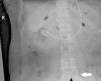

A 52-year-old woman was admitted to the ICU for cardiogenic shock due to viral myocarditis. Despite exhausting maximal efforts, her hemodynamic status continued to deteriorate. The attending physician decided to initiate veno-arterial extracorporeal membrane oxygenation (ECMO) via a percutaneous femoral approach. The left femoral vein and femoral artery cannulas were inserted smoothly. However, low flow occurred immediately after the ECMO run, the ECMO flow was only 0.6L/min at 3000RPM. A bedside abdominal X-ray showed the venous cannula crossing the left iliac vein with its tip located in the right iliac vein (the black arrow in Fig. 1). Immediately after the diagnosis, we stopped ECMO and replanted the femoral vein cannula. Both the abdominal X-ray and echocardiography confirmed that the venous cannula was placed in the inferior vena cava (the black arrow in Fig. 2 and white arrow in Vid. A). As the heart function gradually improved, the patient was successfully weaned from ECMO after 5 days.